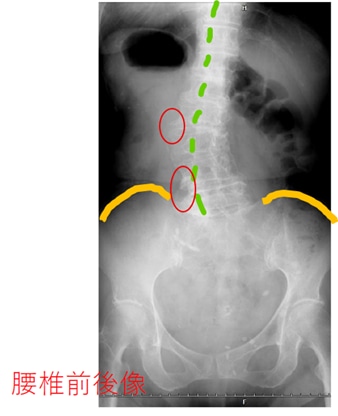

こちらは、

健康を気遣う70代半ばの女性のレントゲンです。

骨盤と腰椎、胸椎が写っています。

慣れない方は分かりづらいので、

ラインを入れて説明しますね。

オレンジは、骨盤の上のライン(腸骨)です。

背骨が真っ直ぐでないことがわかります。

棘突起(背中の正中線を触ると、突起が並んでいます。

魚で言ったら、背びれにあたる突起)に

緑のラインを入れました。

それから、骨棘の分かりやすい所だけ、

赤○で囲んでいます。

外見だけでは、

こんなにも骨が歪んでいることは、

気づけないですよね。

腰痛で整形外科からもらった鎮痛薬を飲んだり、

腰に貼ったりしても、

骨棘が神経に触れていることが原因の

神経痛は、痛いままだと思います。